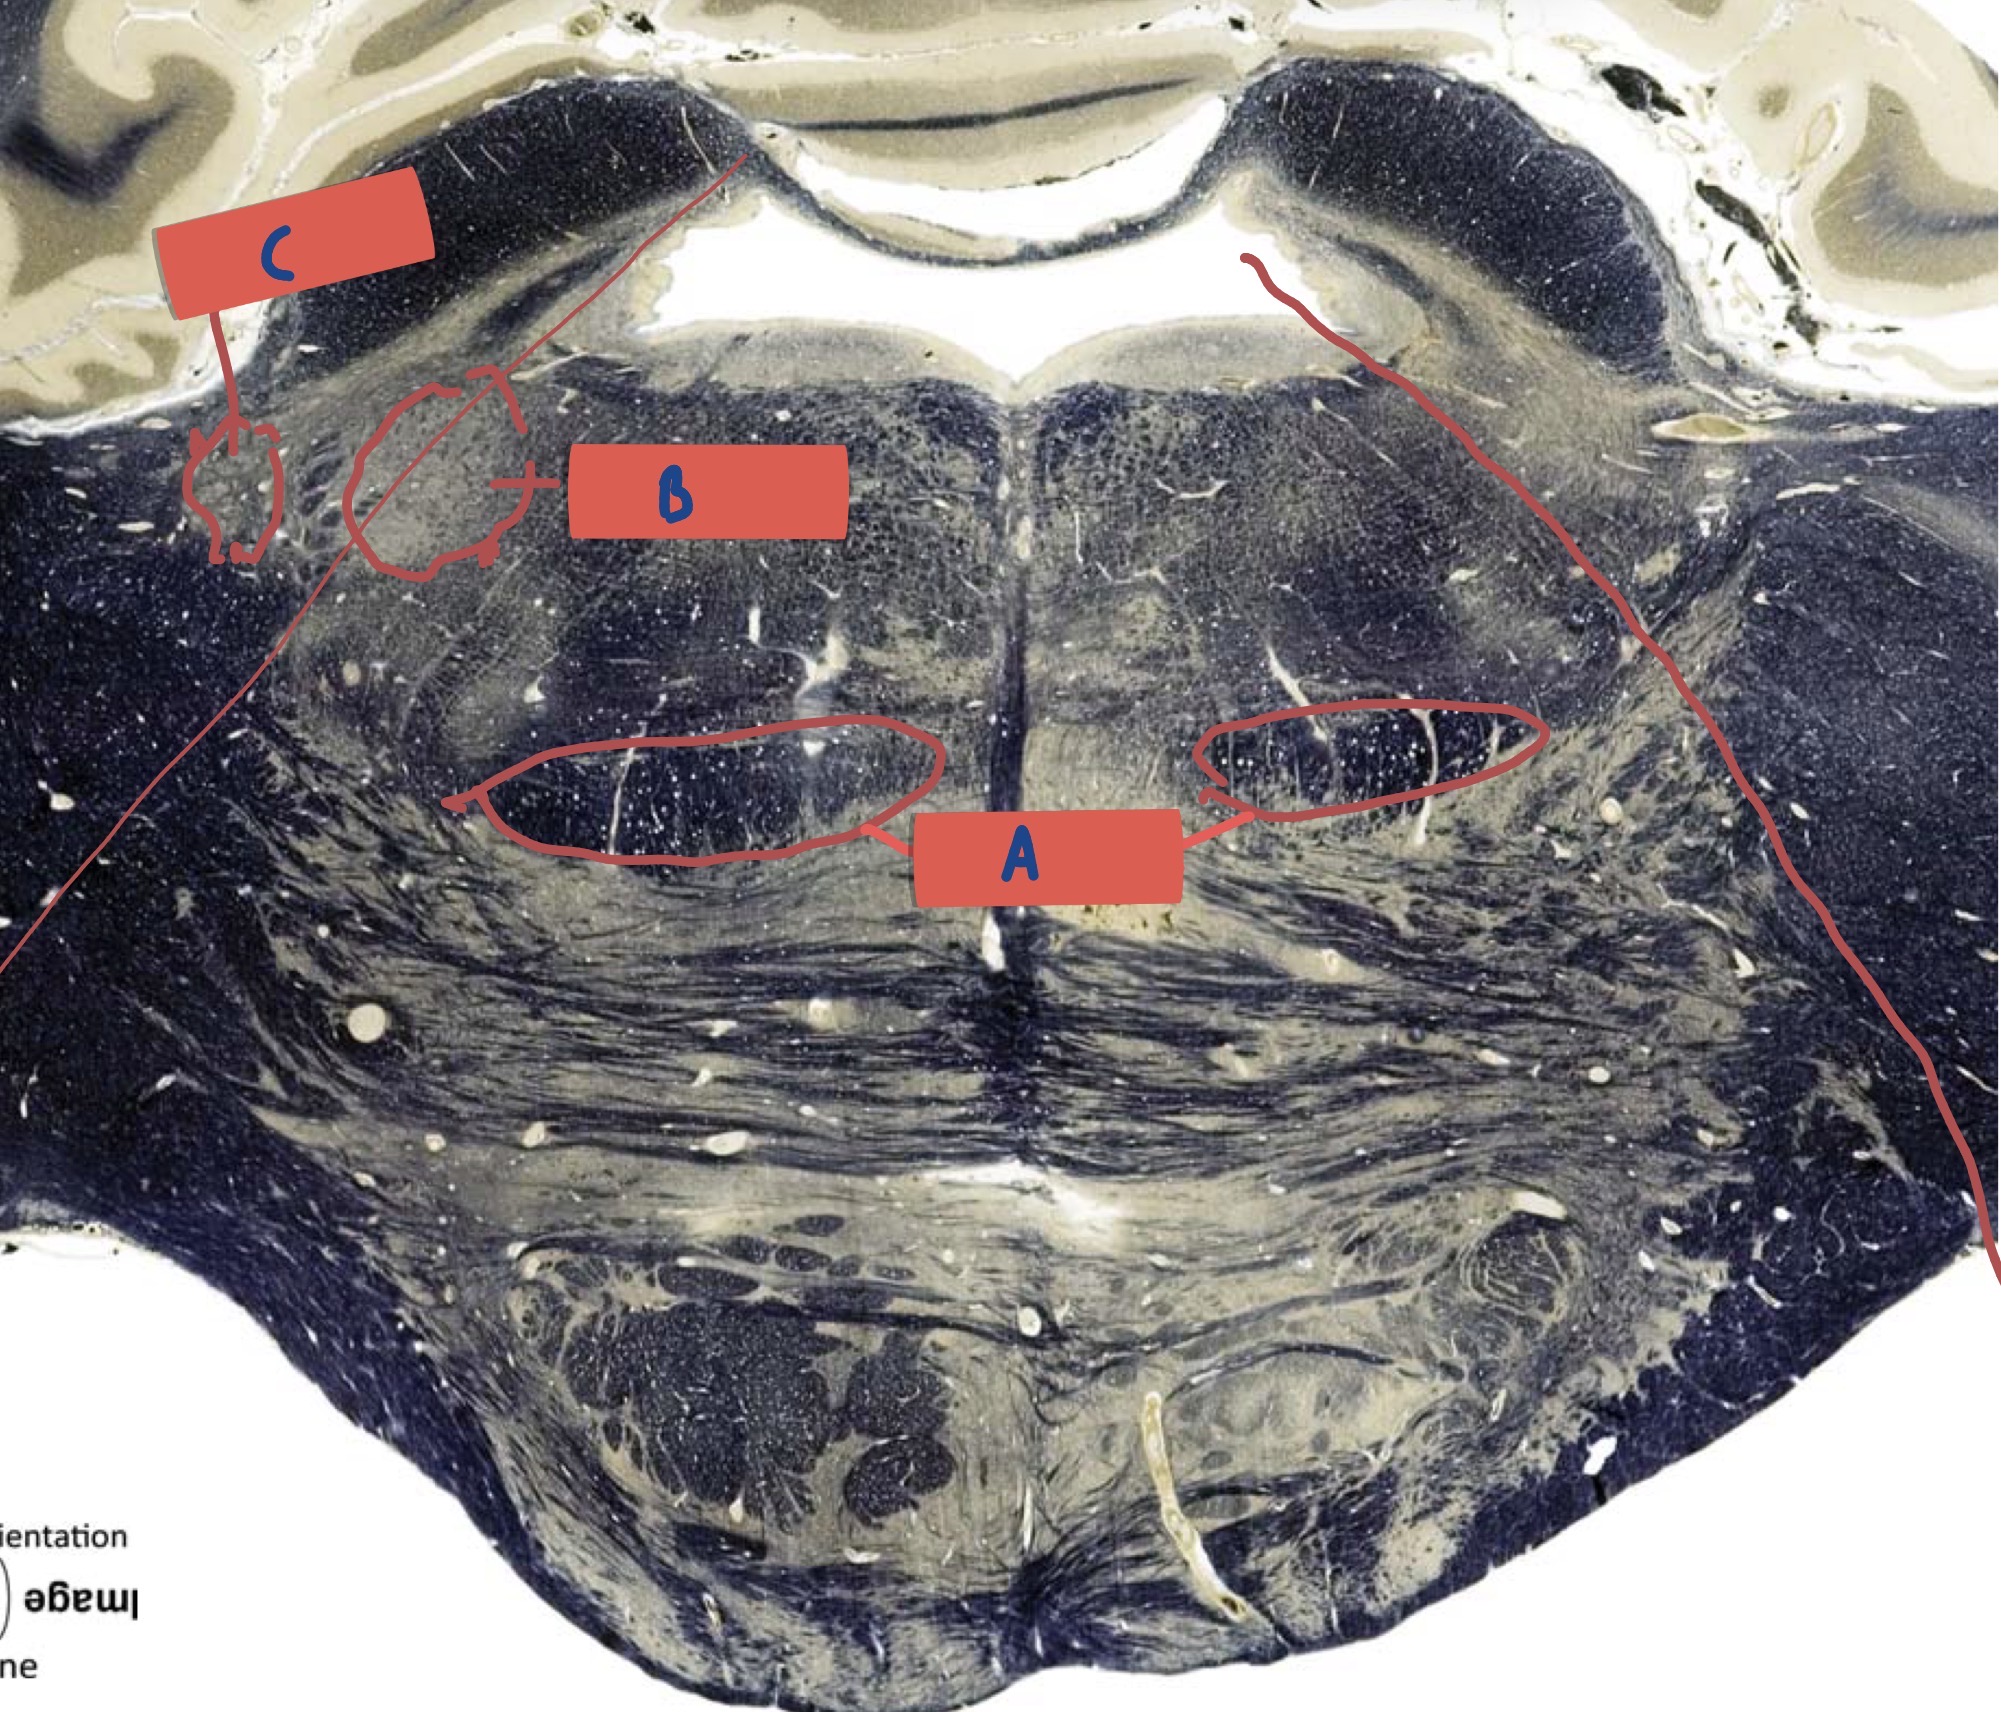

What is A?

Gracile fascicullus

What is B?

Cuneate fasciculus

What is C?

Spinal trigeminal tract

What is D?

Anterolateral System

What is E?

Pyramidal Decussation

What is F

Pyramid

What is G?

Olive

What is H?

Spinal trigeminal nucleus